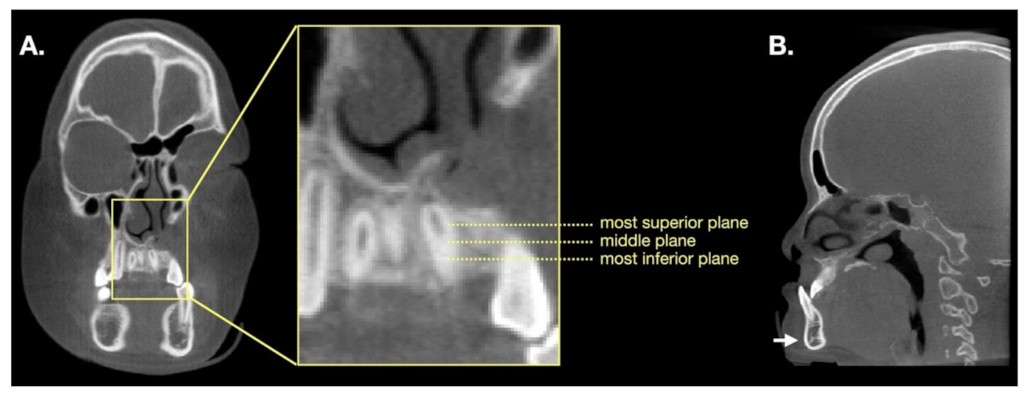

2.2. BMD Measurement and Volumetric Analysis